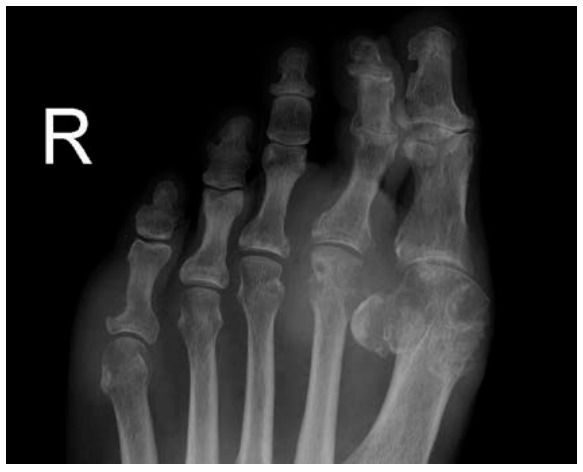

一般發作部位為大拇趾關節(這種情況稱為podagra),踝關節,膝關節等。長期痛風患者有發作於手指關節,甚至耳廓含軟組織部分的病例。急性痛風發作部位出現紅、腫、熱、劇烈疼痛,一般多在子夜發作,可使人從睡眠中驚醒。痛風初期,發作多見於下肢的關節。(痛風大多在半夜才發作是因為晚上睡覺時,人體的抗炎物質促腎上腺皮質激素在半夜時分泌最少,加上睡眠時酸鹼值因體內累積二氧化碳而偏向酸性,而腳趾的溫度較低,加上腳趾附近的液體會被身體吸收使尿酸濃度增加,因此痛風最易在半夜出現在腳拇趾的部位。)